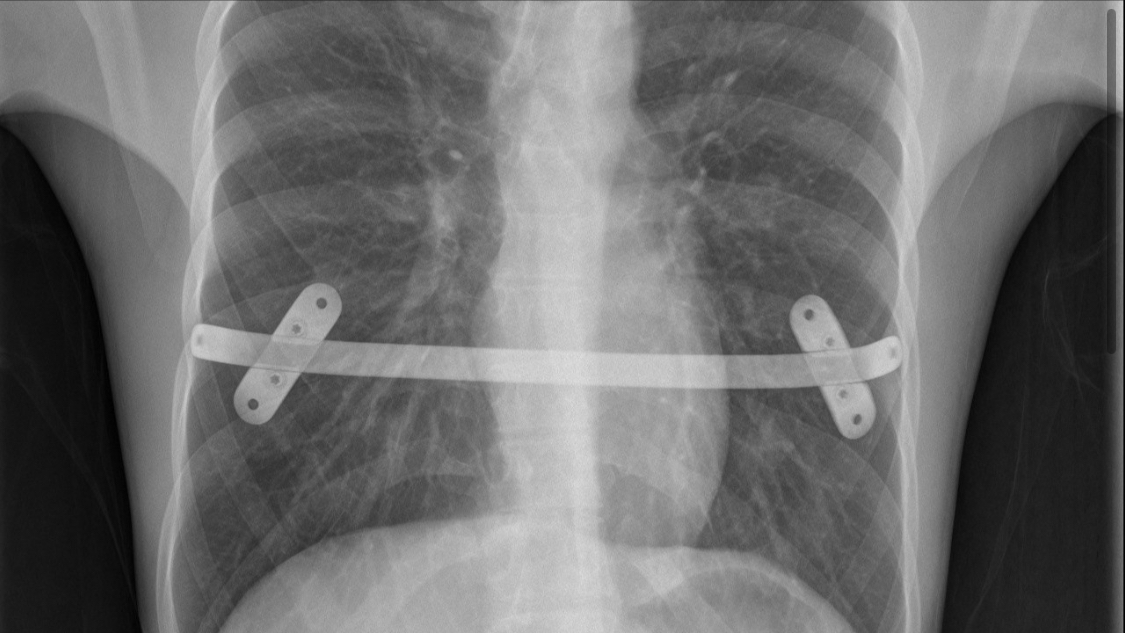

Despite this apparatus, the “consensus” produced Recommendations that in my opinion are debatable, but one of them, in particular, worries me a lot: “For patients with pectus excavatum, the Nuss procedure and the Ravitch procedure have similar surgical risks and efficacy”! This is not true, but still the guideline has already 3650 visualizations in the journal website (on November 11th, 2024).

Is it the end of the minimally invasive repair of pectus excavatum?